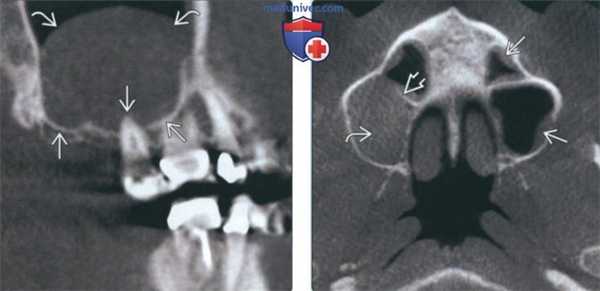

(Слева) На сагиттальной КЛКТ (реконструкций) визуализируется большое куполообразное объемное образование без кортикальной пластинки с плотностью мягких тканей (гиперденсное относительно воздуха), сопоставимое с муцинозной ретенционной псевдокистой верхнечелюстной пазухи. Край пазухи возле кисты интактен.

(Справа) На аксиальной КЛКТ (реконструкция) визуализируется муцинозная ретенционная псевдокиста, занимающая всю камеру правой верхнечелюстной пазухи на этом уровне. Важно не спутать перегородку в пазухе с кортикальной пластинкой на периферии образования. Обратите внимание на утолщение слизистой оболочки камер левой верхнечелюстной пазухи.

(Слева) На периапикальной рентгенограмме задних отделов верхней челюсти справа, не содержащей зубов, на фоне воздуха визуализируется куполообразное затемнение в верхнечелюстной пазухе. Край пазухи возле затемнения интактен. Обратите внимание на наложение скулового отростка.

(Справа) На корональной КЛКТ (реконструкция) визуализируется куполообразная ретенционная псевдокиста в правой верхнечелюстной пазухе. Кортикальная пластинка на периферии псведокисты отсутствует, края пазухи интактны.

(Справа) На аксиальной КЛКТ (реконструкция) визуализируется муцинозная ретенционная псевдокиста, занимающая всю камеру правой верхнечелюстной пазухи на этом уровне. Важно не спутать перегородку в пазухе с кортикальной пластинкой на периферии образования. Обратите внимание на утолщение слизистой оболочки камер левой верхнечелюстной пазухи. (Слева) На периапикальной рентгенограмме задних отделов верхней челюсти справа, не содержащей зубов, на фоне воздуха визуализируется куполообразное затемнение в верхнечелюстной пазухе. Край пазухи возле затемнения интактен. Обратите внимание на наложение скулового отростка.